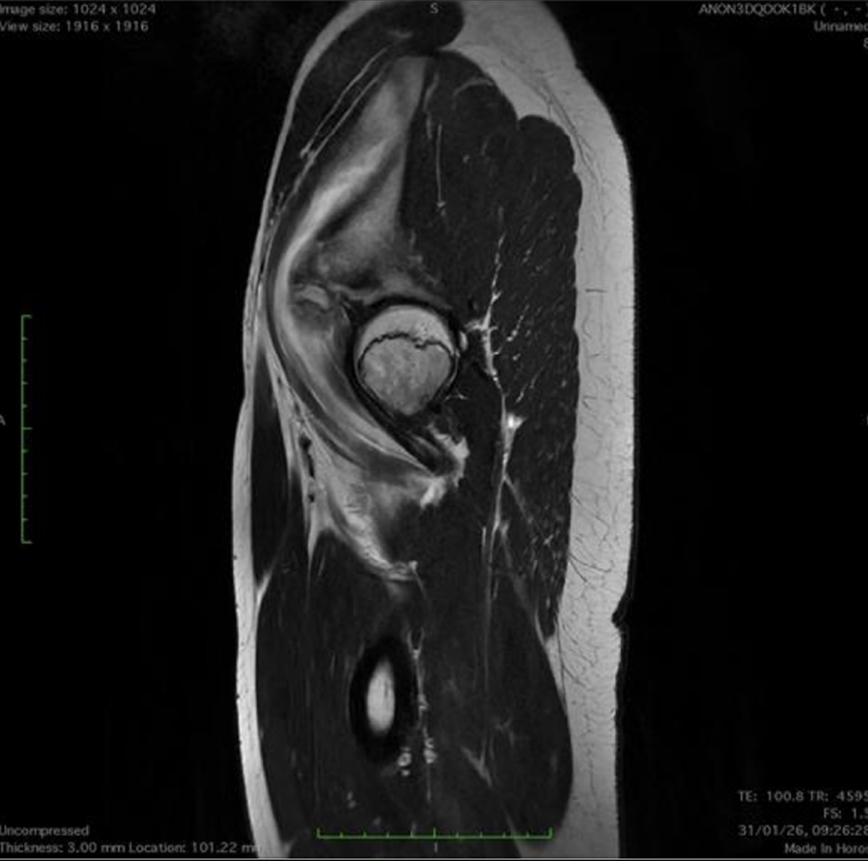

1-Beat Cardiac migliora la qualità diagnostica dell’angio-TC coronarica

L’angio-TC coronarica (CCTA) è uno strumento diagnostico essenziale per l’identificazione delle malattie coronariche, ma la sua affidabilità può essere compromessa nei pazienti con frequenza cardiaca elevata. Grazie ai progressi tecnologici, la modalità 1-Beat Cardiac consente ora di ottenere immagini di alta qualità anche in condizioni di elevata frequenza cardiaca.